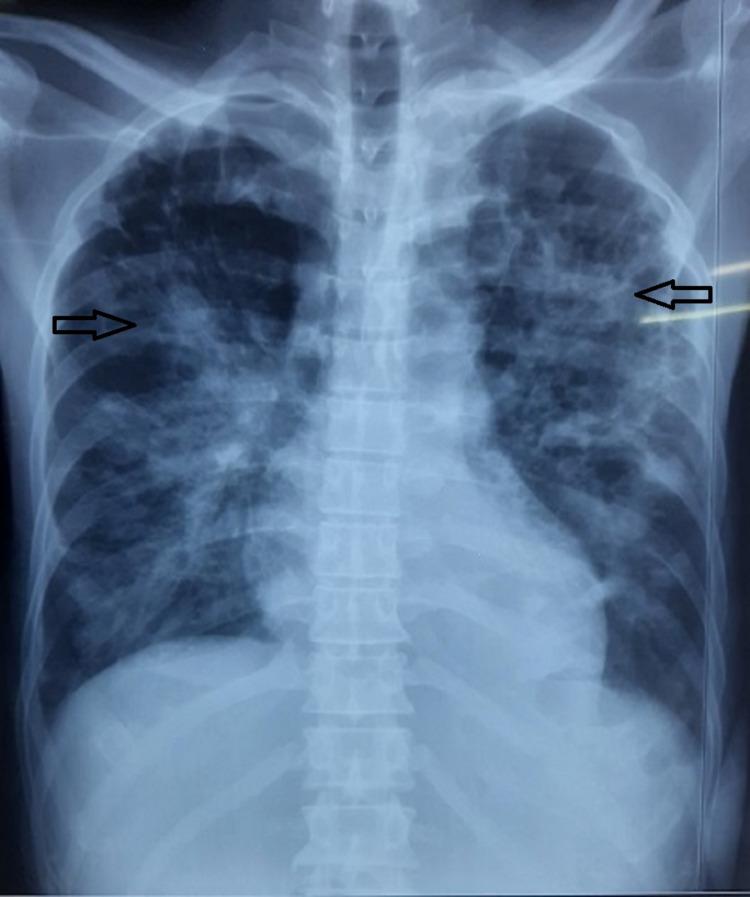

Melioidosis is caused by the Gram-negative bacilli Burkholderia pseudomallei, which is found in contaminated water and soil and spreads via inhalation, inoculation, and ingestion. Melioidosis manifests diversely in immunocompetent and immunocompromised patients, ranging from asymptomatic to life-threatening respiratory distress, septic shock, localized tissue infection, necrotizing pneumonia, and soft organ abscesses.  Methods: An 18-month observational study was conducted at a tertiary center in central India among various confirmed melioidosis cases, with data gathered and analyzed. Aerobic culture and sensitivity were performed in all studied cases, either in blood/body fluid/localized collection - using blood agar media for the culture and disc diffusion method on Mueller Hinton agar for sensitivity. Other tests, such as radiological imaging, were conducted according to symptoms and signs of localized infection.

类鼻疽由革兰氏阴性杆菌伯克霍尔德菌属假鼻疽杆菌引起,该菌存在于受污染的水和土壤中,可通过吸入、接种和摄入传播。类鼻疽在免疫功能正常和免疫功能低下的患者中表现多样,从无症状到危及生命的呼吸窘迫、感染性休克、局部组织感染、坏死性肺炎和软组织脓肿。